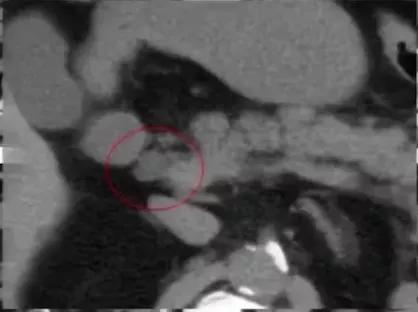

图10:中腹部增强CT显示腹主动脉前后各走行一左肾静脉,分别汇入下腔静脉

图11:腹主动脉两侧均有下腔静脉影,左侧下腔静脉向上与左肾静脉汇合后,在腹主动脉前方绕行,移行为右侧下腔静脉